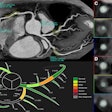

The radiologists conducted their interpretations using dedicated software (V3D Colon, Viatronix) with a 3D-2D hybrid approach for polyp detection, according to the report.